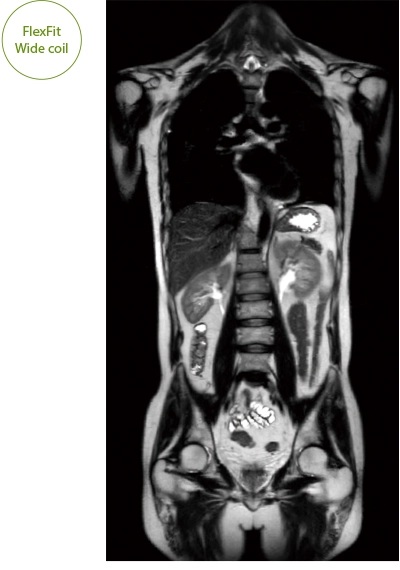

"DLR" is applicable to all body parts and promotes high speed imaging and diagnostic efficiency

IP-RAPID x DLR Plus can also shorten imaging time, allowing more images to be taken in the same examination time.

Additional imaging, such as different image types and cross sections, can be added to the conventional examination to increase the amount of information and make the diagnosis more reliable.

IP-RAPID x DLR Plus gives you the flexibility to shorten respiratory gated series or even replace them with breath-holds, depending on the patient’s situation. This gives you more options and a wider range of examinations to choose from.

IP-RAPID x DLR Plus can be used for basic imaging such as VolumeScan, RadialScan, HalfScan, and many other imaging methods such as MultiContrastScan FatSep and DWI.

It can also be used with time-consuming scans such as Whole Body DWI and Whole Spine imaging, providing more detailed information in many areas than previously possible.